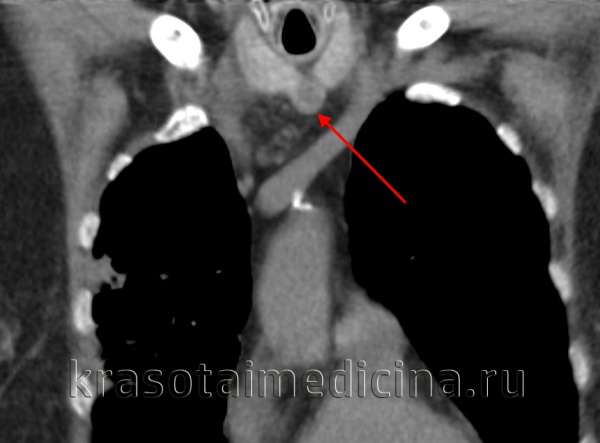

КТ шеи. Слева от средней линии в сонном пространстве кистозное образование (кистозно измененный лимфоузел).